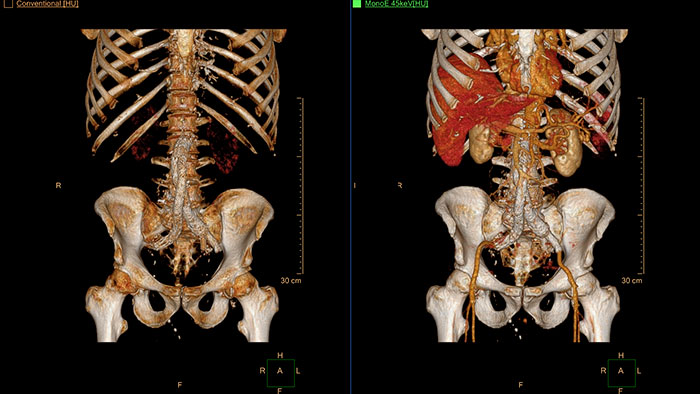

CT Spectral Viewer

IQon Spectral CT* Functionality

The spectral viewer is optimized for analysis of spectral data sets from the IQon Spectral CT Scanner. Obtain a comprehensive overview of each patient quickly and easily, quantify quickly, and assist in diagnosis. It is designed to accommodate general spectral viewing needs with additional tools to assist in CT images analysis.

Benefits

- Enhances the conventional image by overlaying an iodine map.

- Visualization of virtual non-contrast images.

- Images at different energy levels (40-200 keV).

- Switching to various spectral results can be done through a viewport control.

- Manage presets to create user/site-specific presets.

- Lesion characterization using scatter plots.

- Tissue characterization using attenuation curves.

* IQon CT reconstruction provides a single DICOM entity containing sufficient information for retrospective analysis - Spectral Base Image (SBI). SBI contains all the spectrum of spectral results with no need for additional reconstruction or post-processing. Spectral applications are creating different spectral results from SBI.